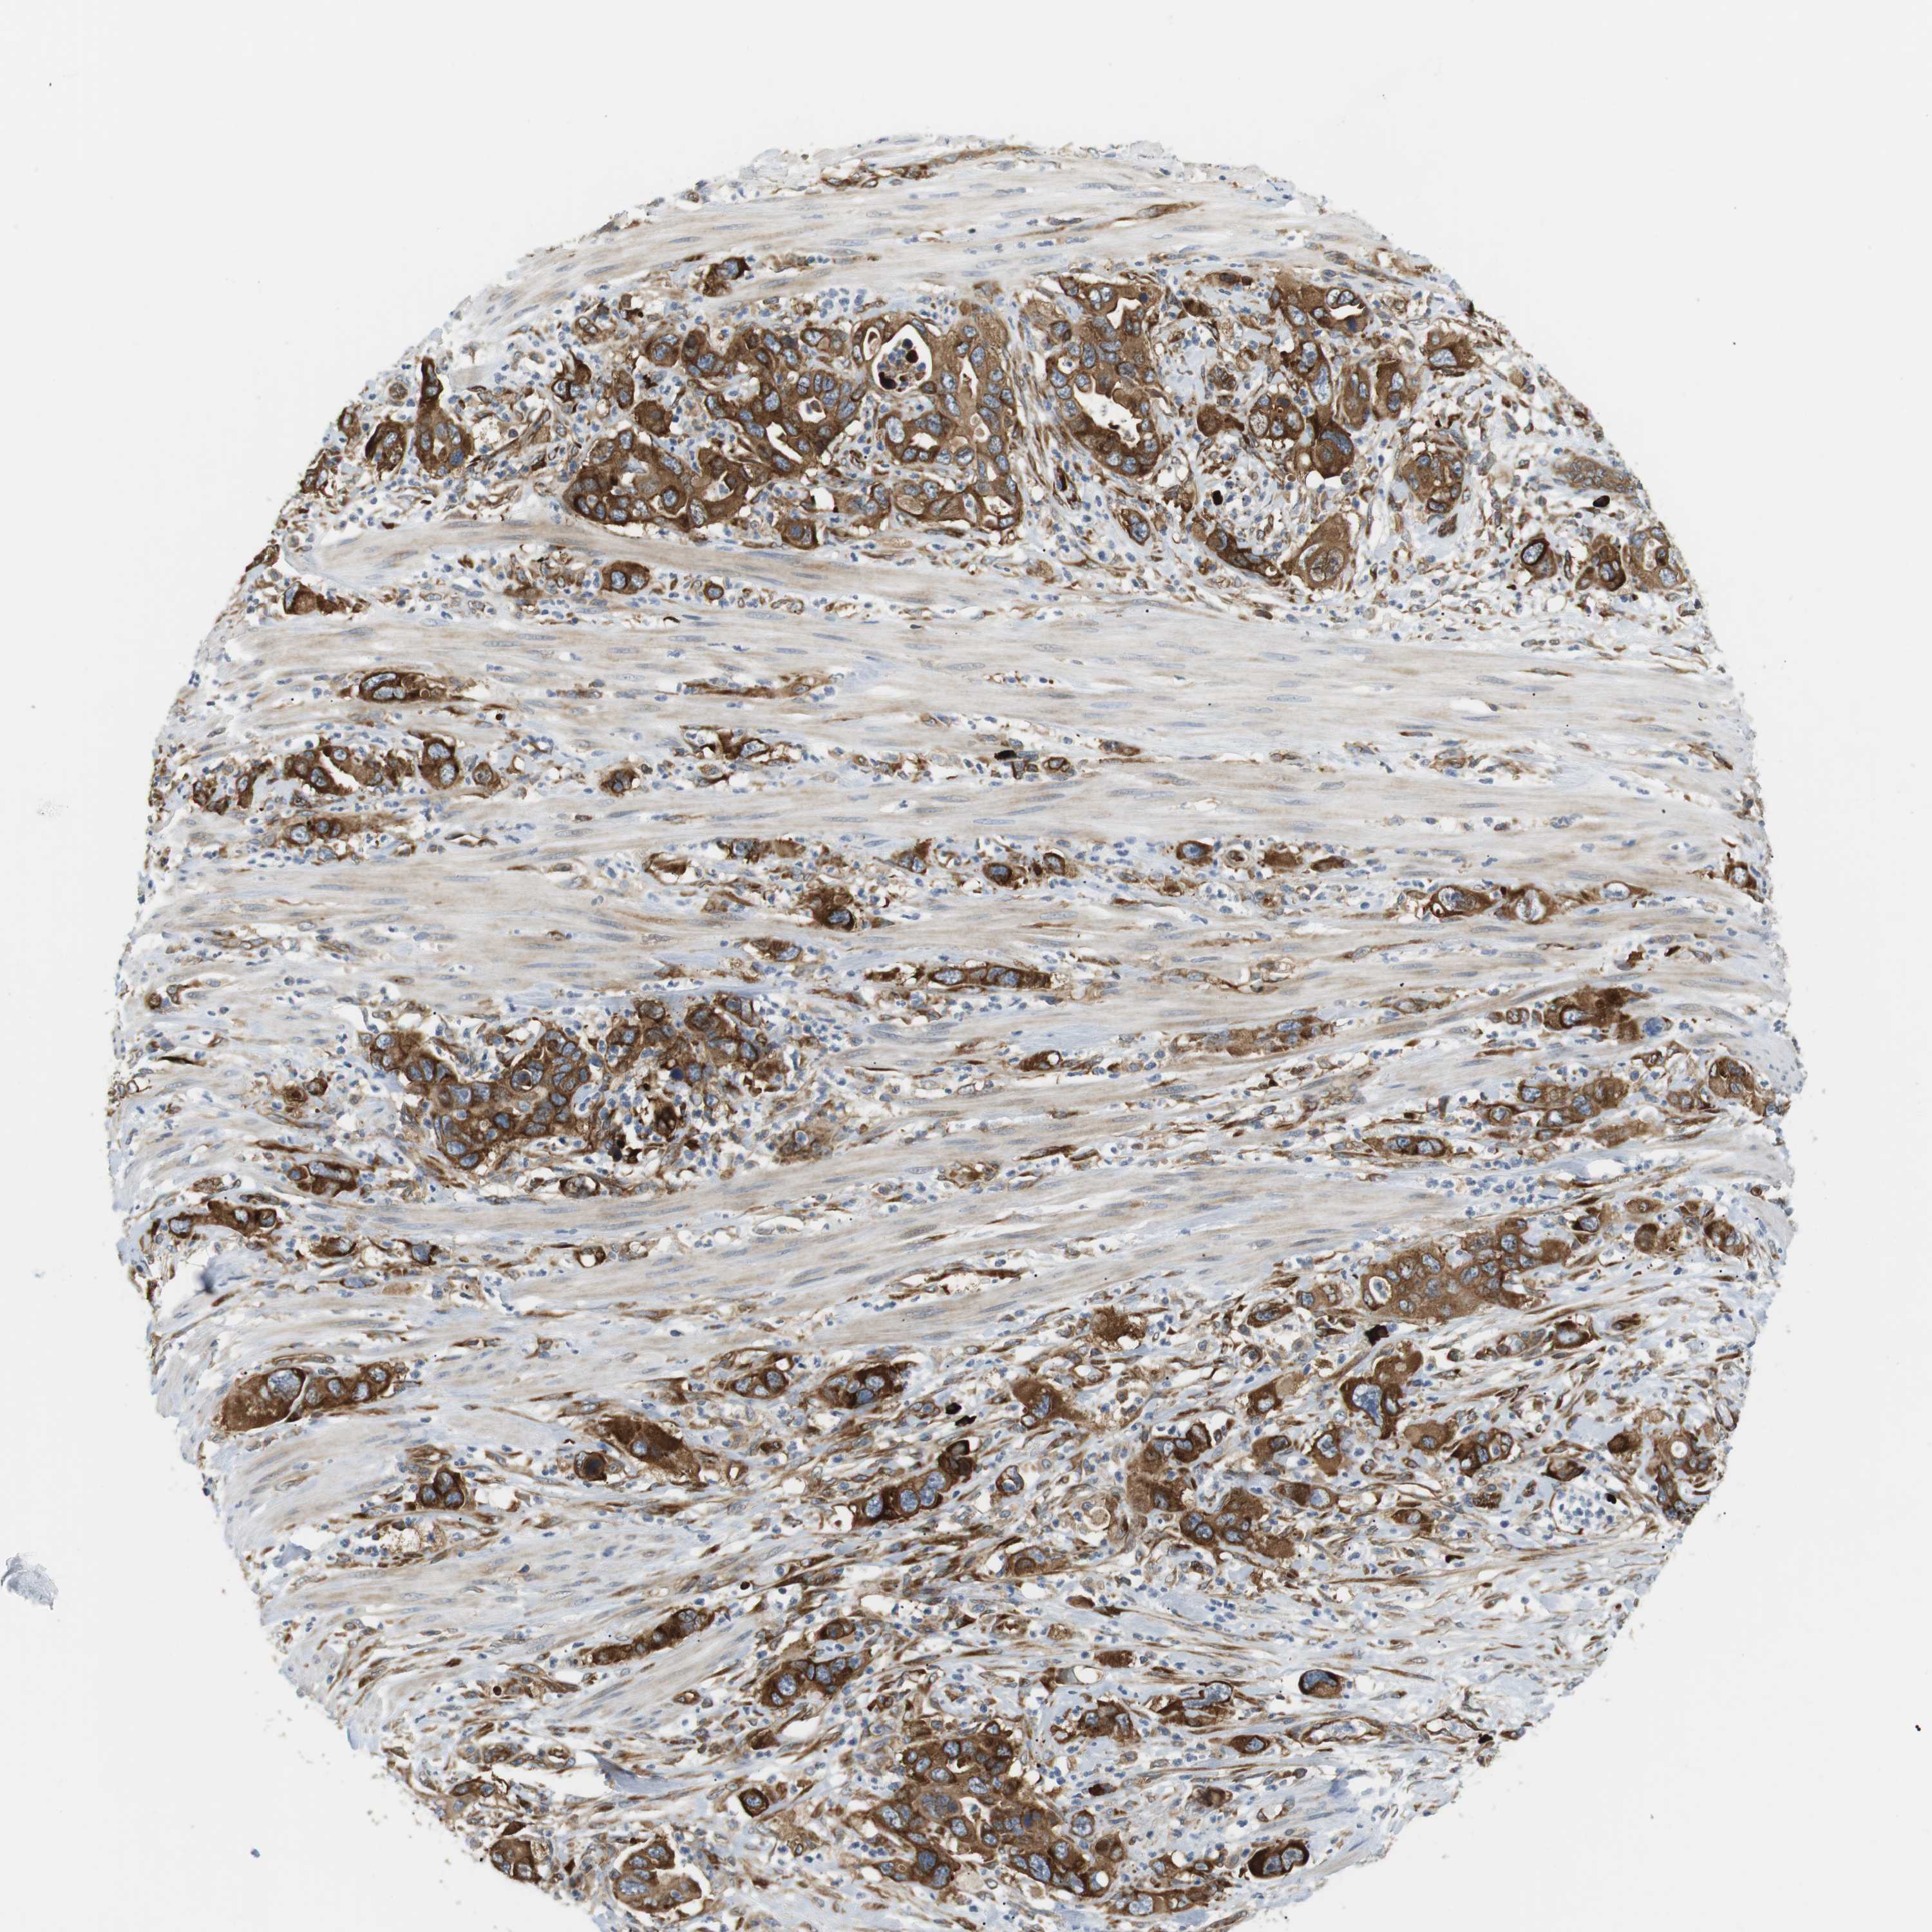

PANCREATIC CANCER - Protein expressioni

A mouse-over function shows sample information and annotation data. Click on an image to view it in a full screen mode. Samples can be filtered based on level of antibody staining by selecting one or several of the following categories: high, medium, low and not detected. The assay and annotation is described here.

Note that samples used for immunohistochemistry by the Human Protein Atlas do not correspond to samples in the TCGA dataset.

Antibody stainingi

Antibody staining in the annotated cell types in the current human tissue is reported as not detected, low, medium, or high, based on conventional immunohistochemistry profiling in selected tissues. This score is based on the combination of the staining intensity and fraction of stained cells.

Each image is clickable and will lead to virtual microscopy that enables deeper exploration of all samples and also displays staining intensity scores, fraction scores and subcellular localization as well as patient and tissue information for each sample.

Antibody HPA014396

Staining

High

Medium

Low

Not detected

Intensity

Strong

Moderate

Weak

Negative

Quantity

>75%

75%-25%

<25%

None

Location

Nuclear

Cytoplasmic/membranous

Cytoplasmic/membranous,nuclear

Adenocarcinoma, NOS